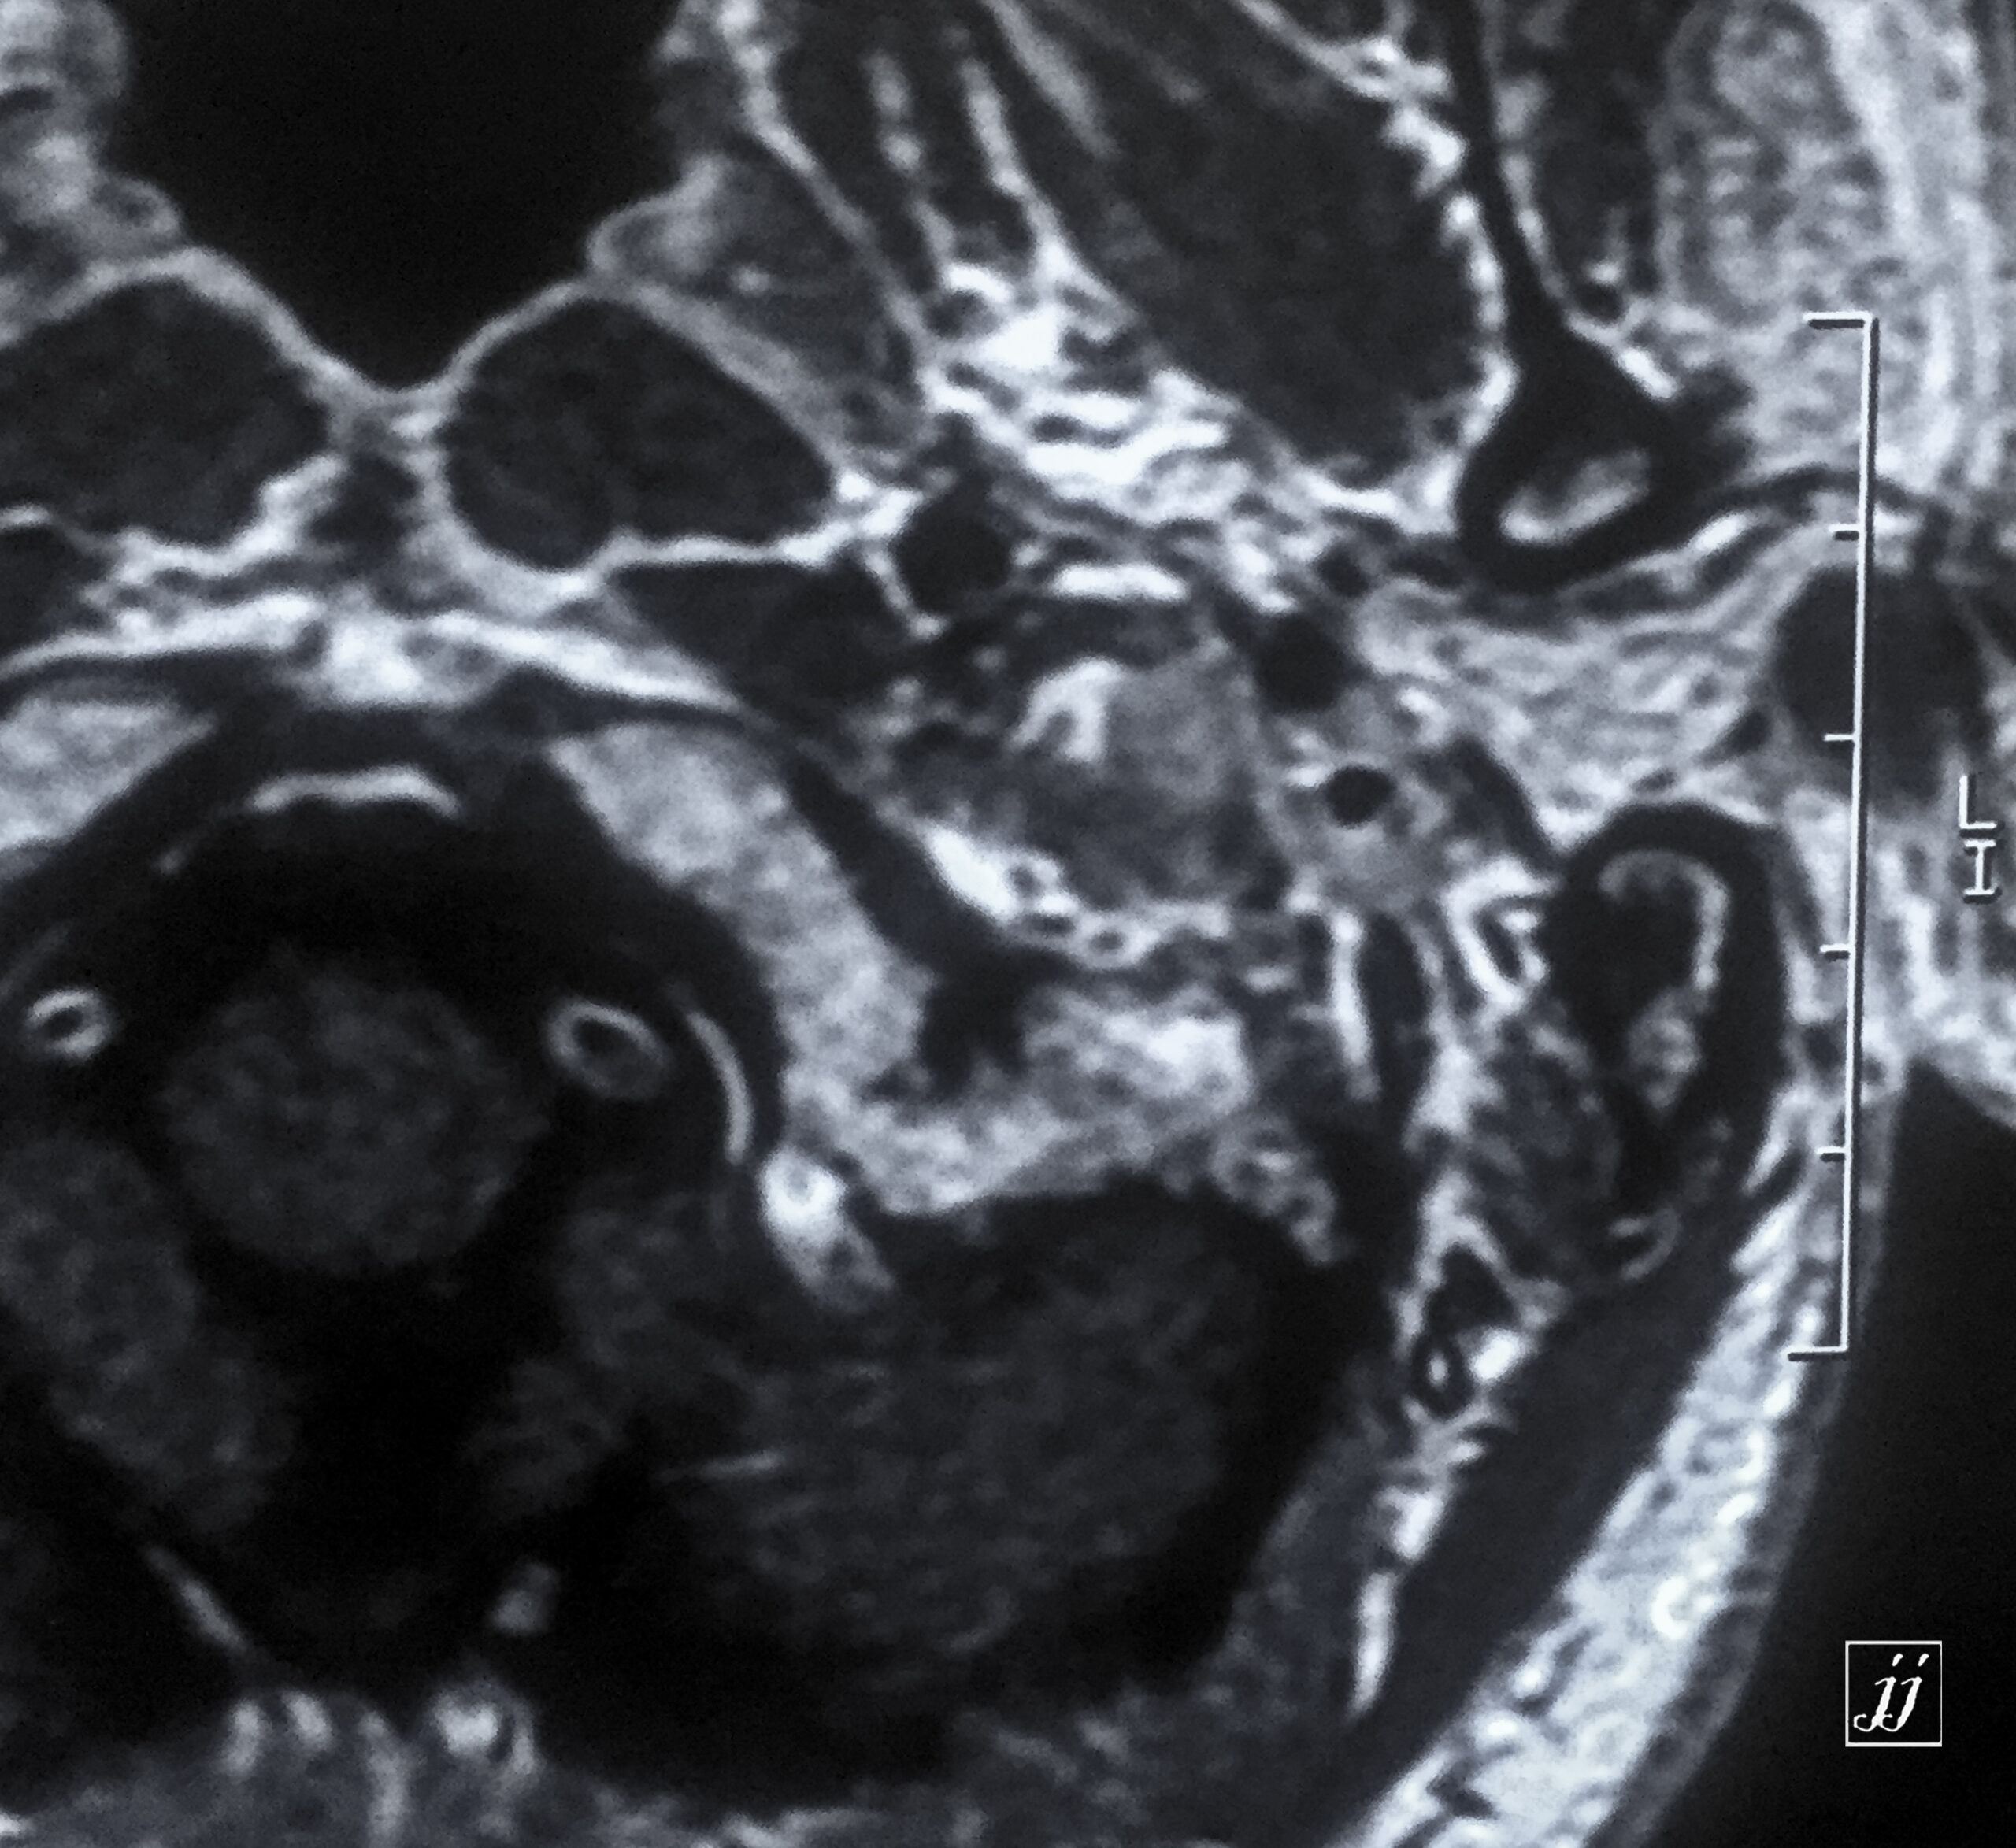

Brain- calcified vertebral arteries (2)